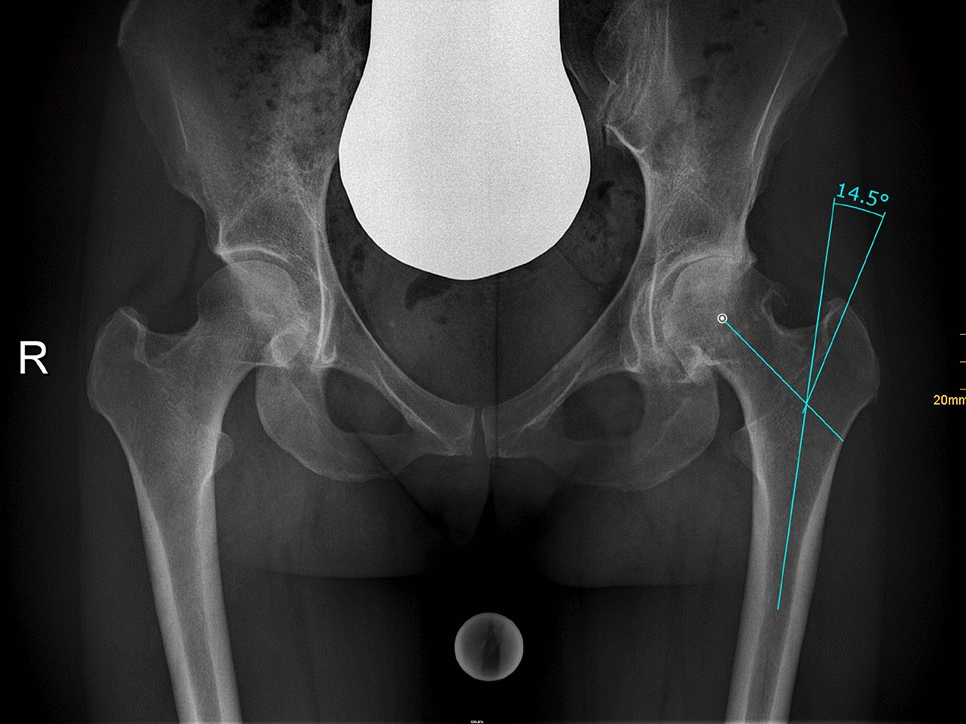

Radiographic measurement was performed on preoperative and 3 months postoperative digital low-centered AP radiographs of the pelvis [17]. Measurements were conducted independently by two reviewers (M.L., J.A.), who were not involved in the index surgery. Radiographs were taken with the patient in standing position and with both legs in 15° internal rotation with the central beam directed on the symphysis pubis [18]. To achieve an accurate measurement of the hip anatomy a double coordinate system was applied on both the preoperative and the postoperative images [1, 19]. Radiographic analysis was performed using MediCAD® Software V5.1 (Hectec GmbH, Germany). The hip center of rotation (COR) was defined using a circle tool determining the diameter of the femoral head and its center [20]. The femoral offset (FO) was determined as the perpendicular distance between the COR and the proximal femoral shaft axis (FSA) [17, 20]. Acetabular offset (AO) was measured as the perpendicular distance between the COR and line T, with T being the perpendicular line on the transteardrop line (TT) through the ipsilateral teardrop figure [17]. Hip offset (HO) was calculated as the sum of FO and AO [17]. The vertical position of the COR was measured as the perpendicular distance to line TT [21]. Radiographic leg length discrepancy (LLD) was measured as the perpendicular distance between line TT and the middle of the lesser trochanter (LT) [18]. Centrum–collum–diaphyseal (CCD) angle was determined according to M. E. Müller on the affected hip [22]. Definition of the stem axis of the implanted cementless stem was previously described for cementless straight stem [23] and for Fitmore® hip stem [24]. For enabling exact measurement of the stem axis of the implanted Fitmore® stem, a digital template of the stem size was put over the implanted stem on the postoperative X-ray. The templating software displayed the correct stem axis of the implanted Fitmore® hip stem, Fig. 3. The critical trochanter angle (CTA) was measured as described by Haversath et al. [7]. The angle crest is defined as the intersection of the femoral shaft axis and the femoral neck axis. A leg between the angle crest and the trochanter vertex is built, and the CTA is measured between this leg and the femoral shaft axis, Fig. 1. To characterize the anatomical shape of the proximal femur and the thickness of cortical bone, the canal to calcar isthmus ratio and the cortical index (CI) according to Dorr et al. [25] were determined. A high CI indicates a thick cortical bone [25]. Additionally, the canal flare according to Noble et al. [26] was determined. The stem alignment was measured as the difference in degrees between the anatomic femoral shaft axis and the vertical stem axis [27]. On preoperative X-rays FO, AO, HO and LLD were measured bilaterally, while CCD angle, CI, Canal Flare Index and canal to calcar ratio were measured unilaterally on the affected hip. Complete preoperative measurements are also shown in Fig. 2.

Fig. 1

Schematic measurement of the critical trochanter angle (CTA)